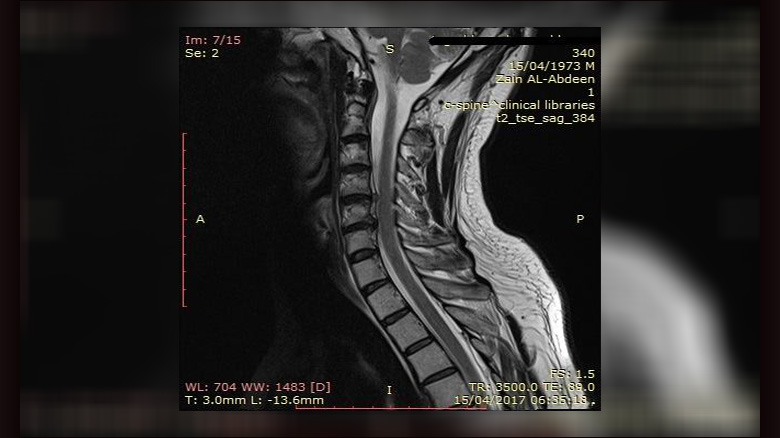

أعلنت مستشفى الإمام زين العابدين عليه السلام التابعة للعتبة الحسينية المقدسة، عن نجاح جديد يضاف الى انجازاتها السابقة، حيث تمكنت كوادرها الطبية من اجراء عملية جراحية  في وضع  (ديسك صناعي) لأحد مرضاها.

وقال فريق الجراحة العصبية في مستشفى الإمام زين العابدين لوكالة نون " نجحنا في اجراء عملية جراحية لمريض كان يعاني من آلام رقبية مع خدر وتنمل في الطرفين العلويين وضعف عضلي، وبعد أجراء الفحوصات الشعاعية تبيّنَ وجود ضغط على الحبل الشوكي، تقررَ على أثره اجراء عملية جراحية". موضحاً" أن العملية أُنجزت بنجاح من خلال استئصال الديسك الضاغط، ووضع ديسك صناعي  (cage) بدلهُ على مستويين مع صفيحة".